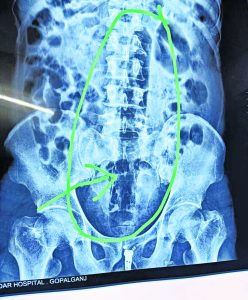

गोपालगंज. गोपालगंज के चनावे मंडल कारा में बंद 45 वर्षीय एक विचाराधीन कैदी ने हैरान करनेवाला कारनामा किया है. कैदी ने अपने गुप्तांग में एक फुट लंबा प्लास्टिक का पाइप डाल लिया. पेट में तेज दर्द होने पर कैदी ने इसकी सूचना जेल कर्मियों को दी, जिसके बाद जेल के अस्पताल में उसे ले जाया गया. हालत बिगड़ने पर कैदी को सदर अस्पताल रेफर कर दिया गया. सोमवार की रात इमरजेंसी वार्ड में भर्ती कराया गया, जहां मेडिकल बोर्ड की टीम ने इलाज शुरू किया. मेडिकल बोर्ड ने एक्सरे जांच करायी, तो रिपोर्ट में कैदी के पेट में एक फुट लंबा पाइप होने का पता चला. बिना ऑपरेशन पाइप नहीं निकल सकेगा, इसलिए डॉक्टरों की टीम ने बेहतर इलाज के लिए पीएमसीएच रेफर कर दिया. वहीं, कैदी ने ऐसा क्यों किया, इसका खुलासा नहीं हो सका है. एक फुट लंबा पाइप किया इंसर्ट : मेडिकल बोर्ड के सदस्य और कैदी का इलाज कर रहे सदर अस्पताल के चिकित्सक डॉ विमान केसरी का कहना है कि एक्सरे जांच रिपोर्ट में साफ नजर आया कि रीढ़ की हड्डी के पास एक लंबा पाइप के आकार जैसा वास्तु फंसा हुआ है. इसकी लंबाई तकरीबन एक फुट तक और मोटाई एक इंच से आसपास होने की संभावना है. डॉक्टर ने कहा कि कैदी ने खुद से पाइप को इंसर्ट करने की बात बतायी है. कैदी ने ऐसा क्यों किया, इसके बारे में उसने कुछ नहीं कहा है. डॉक्टर ने कहा कि सदर अस्पताल में इतना बड़ा ऑपरेशन करने के लिए तत्काल इंतजाम नहीं हो सकेगा, इसलिए चिकित्सकों की बोर्ड ने कैदी को बेहतर इलाज के लिए पीएचसीएच रेफर किया गया है. कड़ी सुरक्षा के बीच जेल की एंबुलेंस से कैदी को लाया गया था और सदर अस्पताल से पीएमसीएच रेफर किया गया है. जेल के सूत्रों ने बताया कि बरौली थाना क्षेत्र का रहनेवाला विचाराधीन कैदी हत्या के प्रयास के एक मामले में चनावे मंडल कारा में बंद है. रविवार की रात उसने अपने गुप्तांग में प्लास्टिक का पाइप डाल लिया. उसके बाद उसने पाइप को खुद से निकालने की कोशिश की. तब पाइप और भी अंदर की ओर चला गया. इसके बाद परेशानी बढ़ने लगी और उसने मंडल कारा के कर्मियों को इसकी सूचना दी. सोमवार को पूरे दिन मंडल कारा में ही उसका इलाज हुआ. हालत नहीं सुधरने पर बेहतर इलाज के लिए सदर अस्पताल के इमरजेंसी वार्ड में भर्ती कराया गया, जहां अस्पताल प्रशासन ने मेडिकल बोर्ड का गठन कर कैदी का इलाज शुरू कराया मेडिकल बोर्ड ने भी देर रात पीएमसीएच रेफर कर दिया.